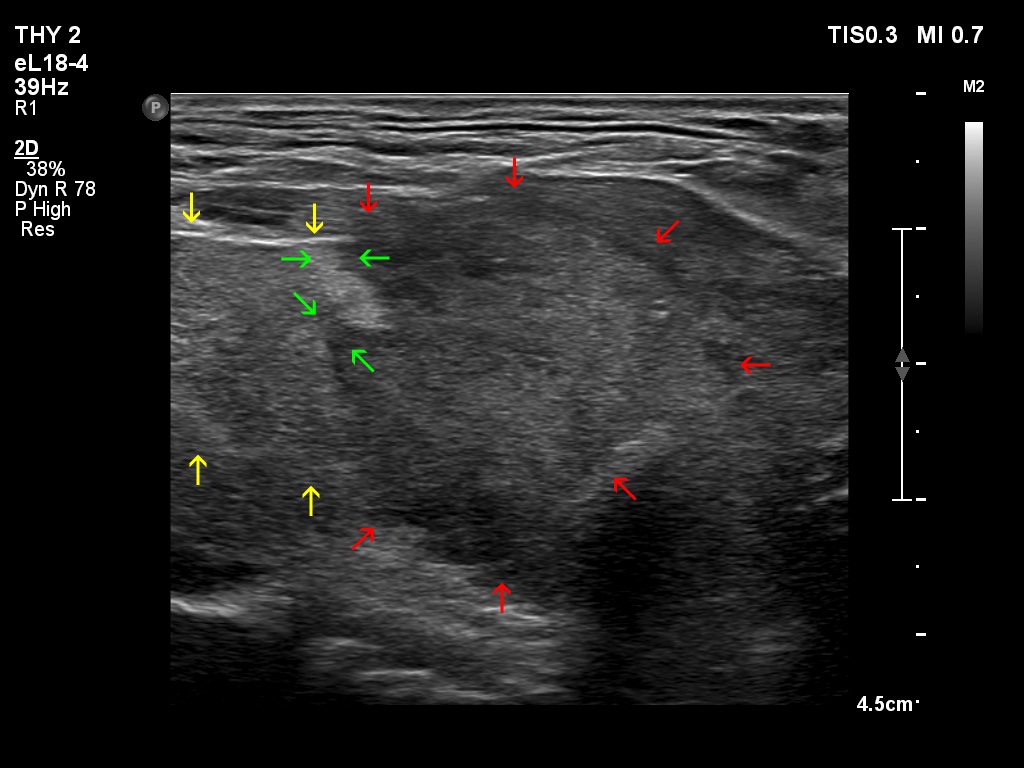

Teamwork - case 378 (ultrasonographic picture 3b)

Right thyroid bed, longitudinal scan. Yellow arrows point to the lower part of the right thyroid lobe, while red arrows point to the tumor which is located under the thyroid. Note the infiltrative margins of the tumor (green arrows).